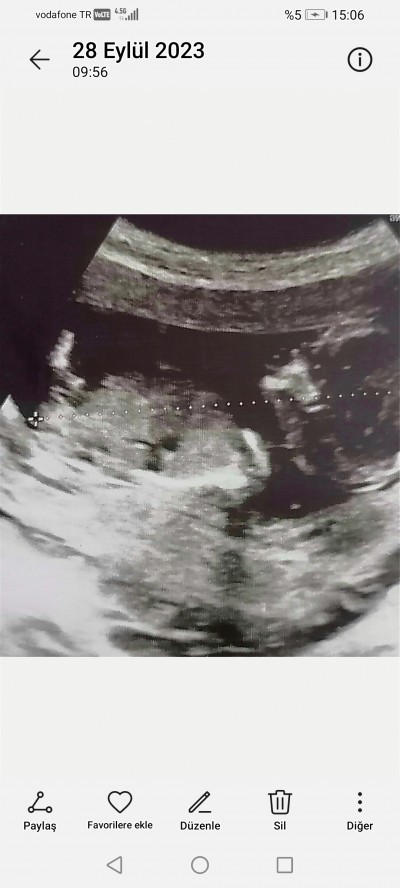

13 haftalık 3 gunluk doktora cinsiyet hakkında hiçbirsey söylemedi merak ediyorum nub teorisi dogruluk payı cok oldugunu duydum sizce ne olabilir cinsiyeti